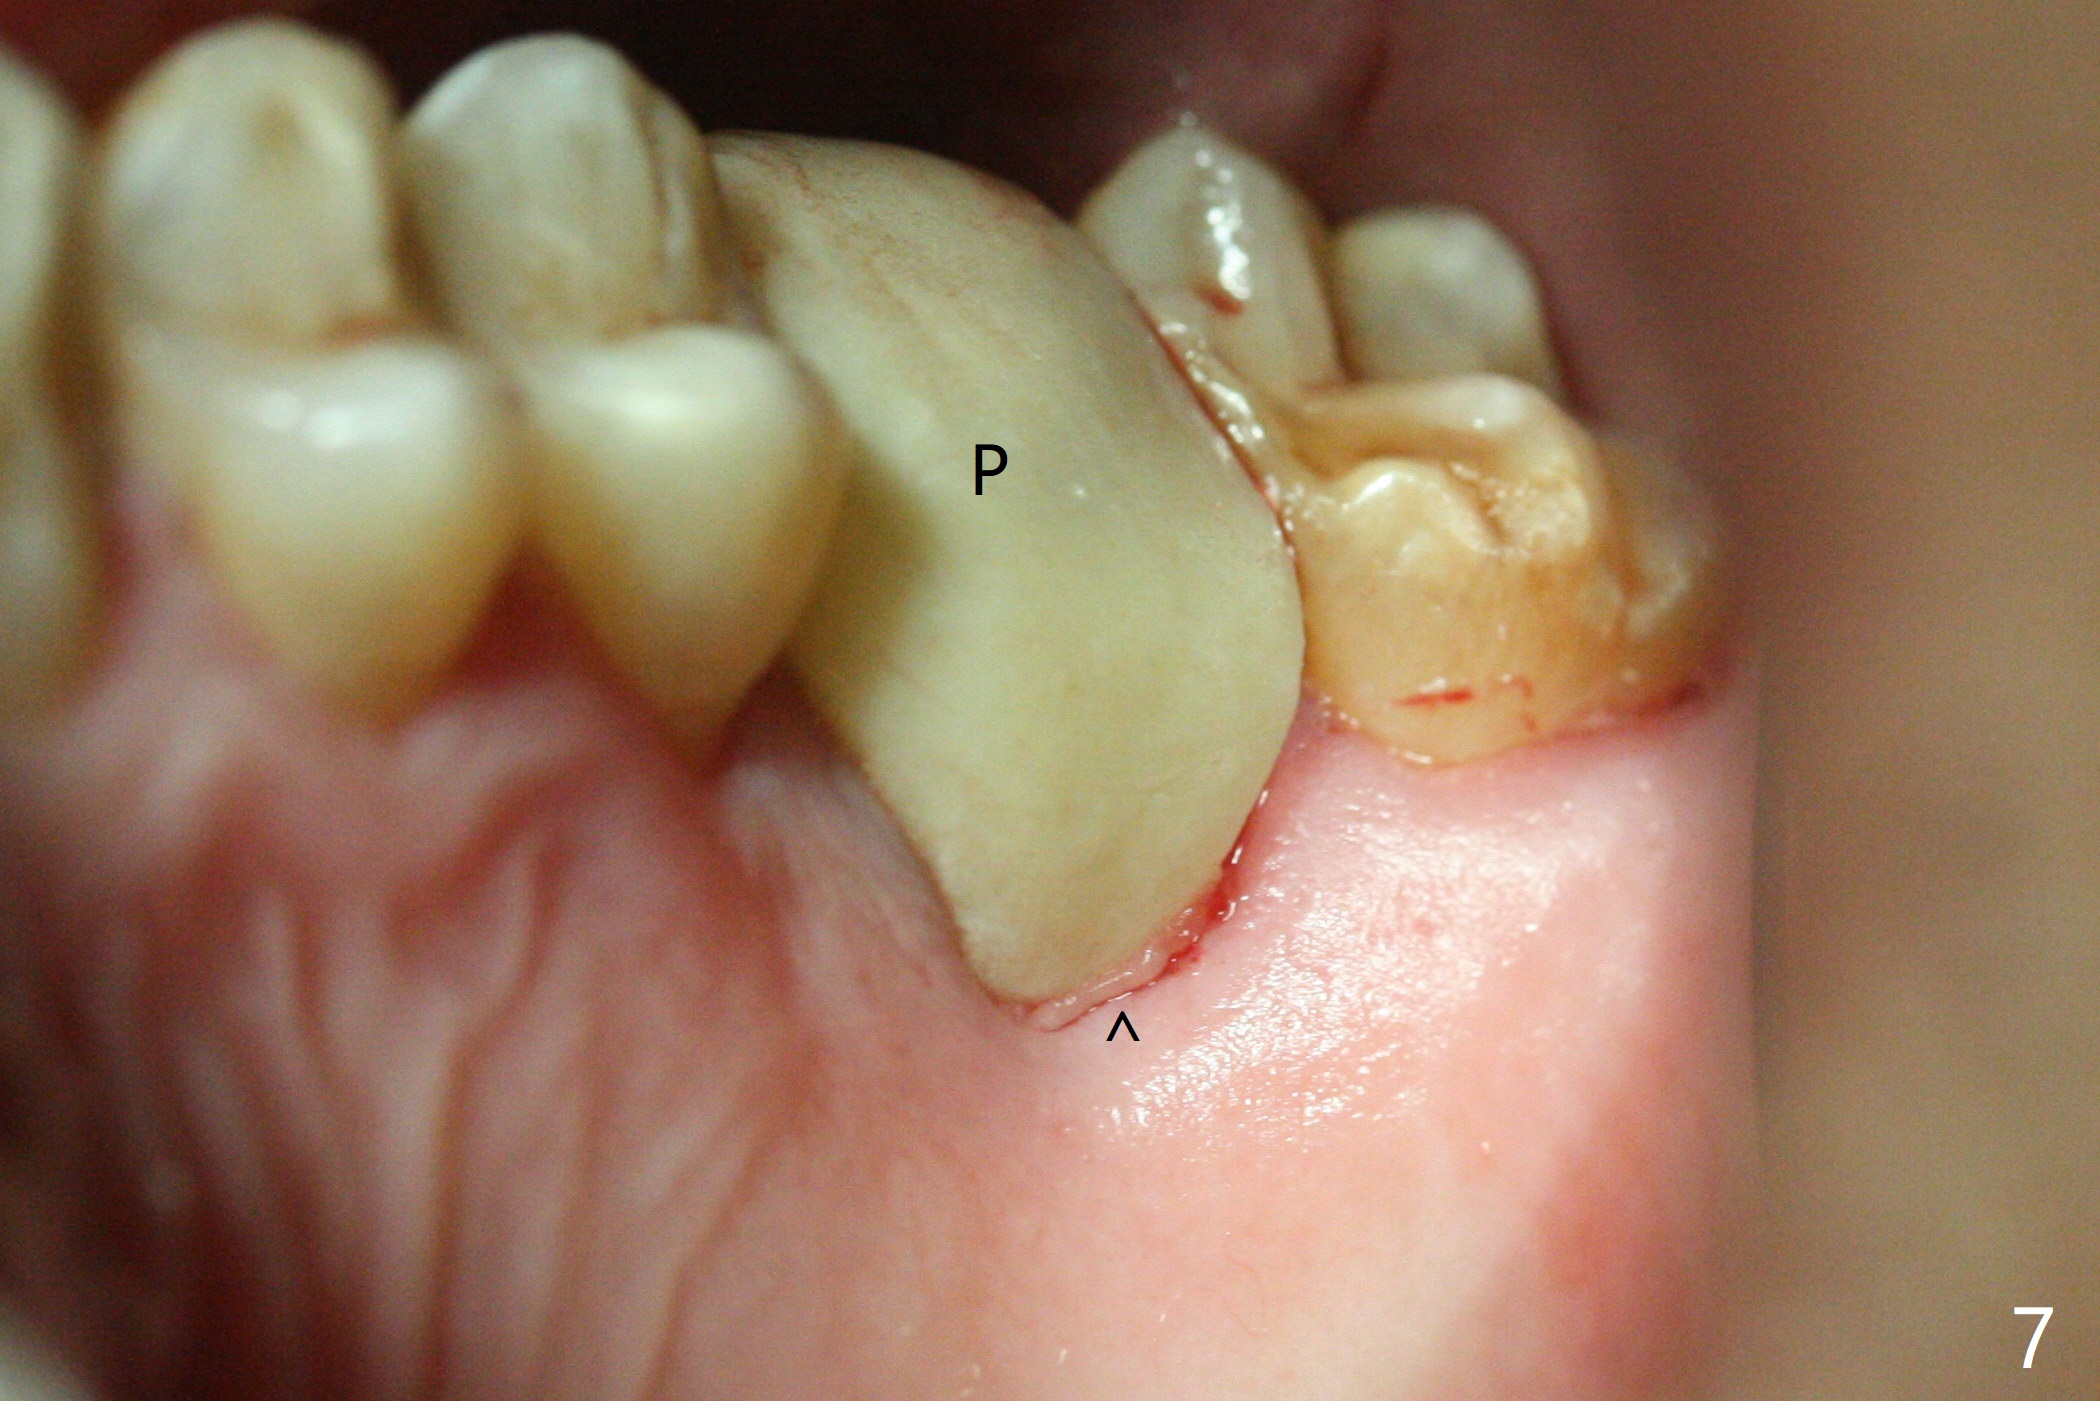

With modification of drill sequence in the last 3 steps (4.5x7.3, 4.0x8.5 and 3.5x10 mm drills) at #14 and sinus lift (Fig.1), a 5x9 mm implant is placed with ~ 50 Ncm following back up twice. Sticky bone mixed with autogenous bone (Fig.1,2 white *) is placed in the sockets before and after placement of a 6.5x5.7(2) mm abutment. Since the palatal gingival margin is recessive (Fig.3 ^), a palatal socket shield retains to prevent further recession (Fig.4 in the end of periodontal probe). Because the margin of the abutment is low, it changes to one with longer cuff (Fig.5). An immediate provisional is fabricated (Fig.6,7 P). The bone graft is indistinguishable from the original alveolus 9 months postop (Fig.8 *). The palatal socket shield is exposed 10 months postop (Fig.9 <). Since the implant is intentionally placed buccal; the sheath is not essential.